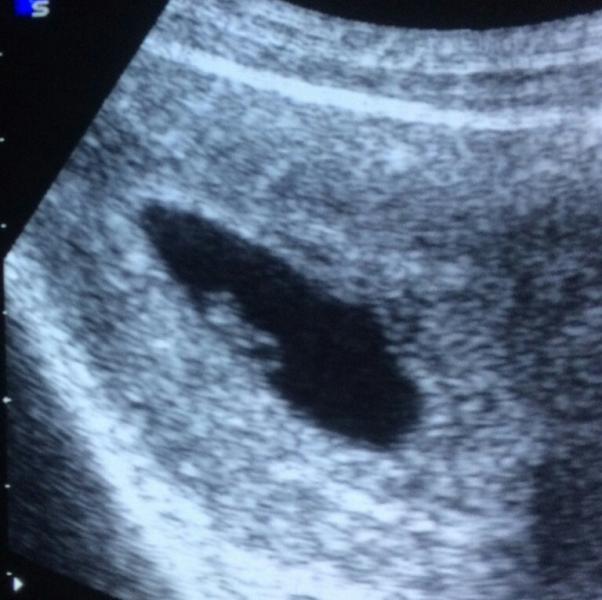

Пока узистка крутила головой, я быстро сделала наше первое фото )))

@boje_vilna мы делали первое УЗИ ещё в 4 недели(Врач поставил строк 9 недель и послал на УЗИ, как оказалось 4 недели.Но мы уже были 7 мм)))А вы какого размера?

@katuha-vl наверное))) этого узи не должно было быть. но из-за угрозы срыва пришлось сделать)) сказали - жопастый красавчик)))